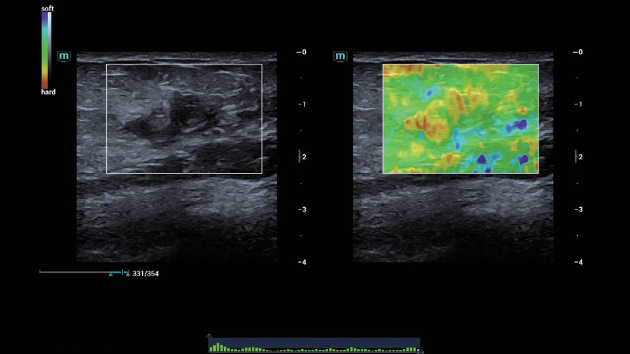

Solu??es abrangentes de imagens com tecnologia ZST+

A plataforma ZST+ ÃĐ uma inova??o extraordinÃĄria, representando a evolu??o do ultrassom. Transformando as mÃĐtricas de ultrassom: da forma??o convencional do feixe ao processamento baseado em dados de canais. Supera a limita??o de compensa??o tradicional entre resolu??o espacial, resolu??o temporal e uniformidade de tecido, oferecendo qualidade de imagem excepcional para solu??es de imagem infinitas com melhorias inigualÃĄveis.